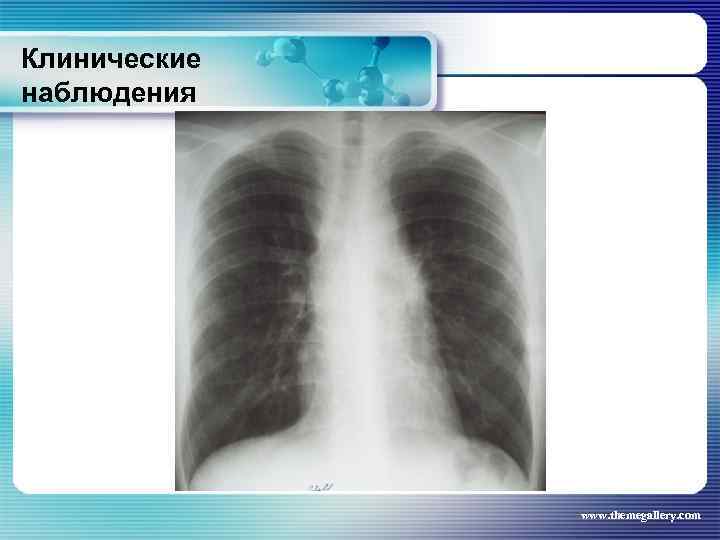

Клинические наблюдения Больной М. , 22 лет Заболел в январе 2010 года, когда появился мучительный кожный зуд, похудание, прогрессивный рост лимфатических узлов на шее, затрудненное дыхание. Самостоятельно обратился в поликлинику, направлен в гематологическое отделение. Выполнена биопсия шейного лимфатического узла: Лимфома Ходжкина. , нодулярный склероз Grade I. Уже отделении появилась лихорадка. При лабораторном обследовании выявлены признаки выраженной активности процесса. Результаты лучевого обследования: www. themegallery. com

Клинические наблюдения Больной М. , 22 лет Заболел в январе 2010 года, когда появился мучительный кожный зуд, похудание, прогрессивный рост лимфатических узлов на шее, затрудненное дыхание. Самостоятельно обратился в поликлинику, направлен в гематологическое отделение. Выполнена биопсия шейного лимфатического узла: Лимфома Ходжкина. , нодулярный склероз Grade I. Уже отделении появилась лихорадка. При лабораторном обследовании выявлены признаки выраженной активности процесса. Результаты лучевого обследования: www. themegallery. com

Клинические наблюдения Больной М. , 22 лет По результатам обследования сформулирован клинический диагноз: лимфома Ходжкина, нодулярный склероз, Grade I, III В стадия с поражением подчелюстных, шейных, надключичных лимфатических узлов с обеих сторон, подмышечных, переднегрудных, парастернальных, внутригрудных и абдоминальных лимфатических узлов, средостения. Было проведено 8 циклов BACOPP, на фоне лечения осложнение: полинейропатия рук, а затем асептический некроз головки правой бедренной кости. На фоне терапии отмечена положительная динамика как лабораторных данных, так и результатов лучевого обследования. Констатирована ремиссия www. themegallery. com

Клинические наблюдения Больной М. , 22 лет По результатам обследования сформулирован клинический диагноз: лимфома Ходжкина, нодулярный склероз, Grade I, III В стадия с поражением подчелюстных, шейных, надключичных лимфатических узлов с обеих сторон, подмышечных, переднегрудных, парастернальных, внутригрудных и абдоминальных лимфатических узлов, средостения. Было проведено 8 циклов BACOPP, на фоне лечения осложнение: полинейропатия рук, а затем асептический некроз головки правой бедренной кости. На фоне терапии отмечена положительная динамика как лабораторных данных, так и результатов лучевого обследования. Констатирована ремиссия www. themegallery. com

Клинические наблюдения Тот же пациент В сентябре-ноябре 2010 года выполнена телегамматерапия на шейные, надключичные лимфатические узлы, средостение (СОД – 36 Гр) и на аксилярную область (СОД – 24 Гр). Абдоминальные лимфатические узлы не облучали, т. к. они регрессировали на фоне ПХТ. Результаты лучевого обследования в настоящее время: www. themegallery. com

Клинические наблюдения Тот же пациент В сентябре-ноябре 2010 года выполнена телегамматерапия на шейные, надключичные лимфатические узлы, средостение (СОД – 36 Гр) и на аксилярную область (СОД – 24 Гр). Абдоминальные лимфатические узлы не облучали, т. к. они регрессировали на фоне ПХТ. Результаты лучевого обследования в настоящее время: www. themegallery. com